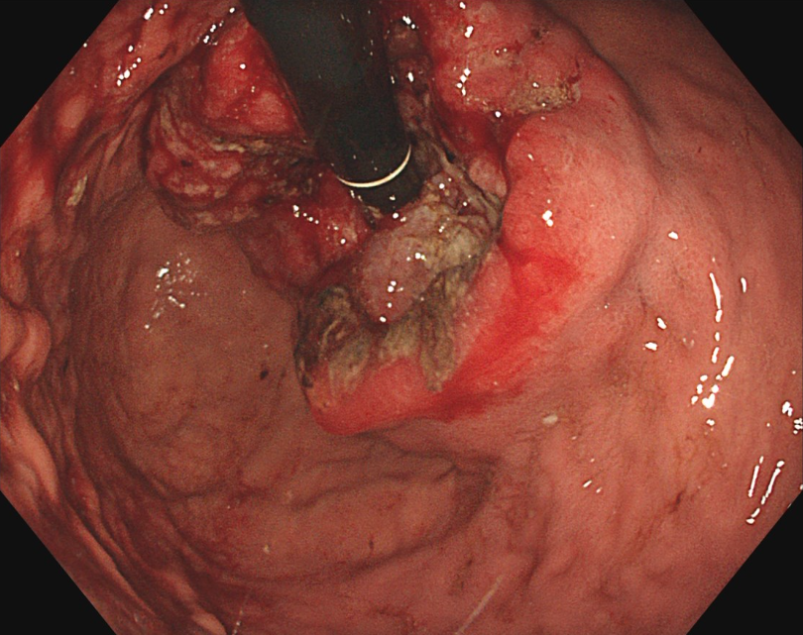

内視鏡(胃カメラ)画像

胃カメラを挿入して直接観察する内視鏡検査が行われます。進行度を判断するための検査では、造影CT検査、MRI検査、PET検査などを組み合わせて、がんの深さやリンパ節および周辺臓器への転移がないかを診断します。また、補助的に血液中の腫瘍マーカーの値を見る検査も行います。